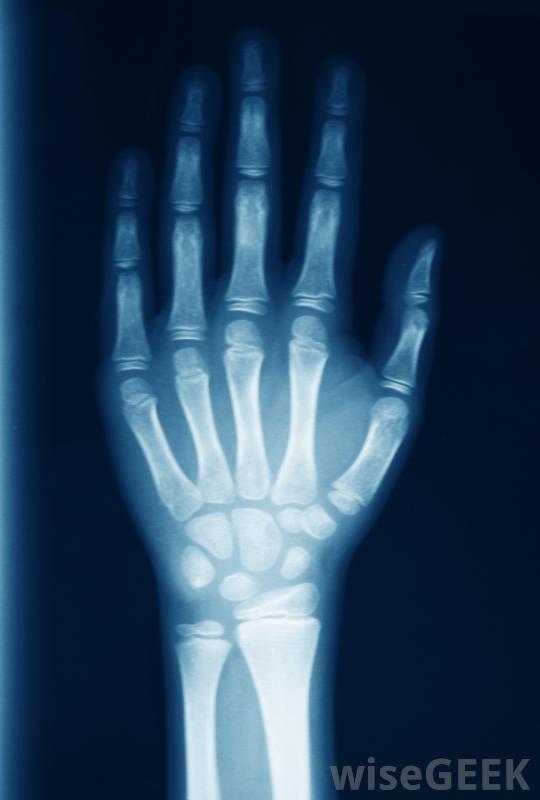

什么問題會影響手腕軟骨(What Problems Affect Wrist Cartilage)?

人類的手腕是一個非常獨特的關節,因為它既是身體中最靈活也是最強壯的關節之一。它必須是靈活的,以允許手有廣泛的運動范圍,并且非常穩定,以允許手拿起和操縱重物。關節、骨骼、肌腱,而組成腕部的韌帶則依靠軟骨來緩沖,防止嚴重傷害。當手腕軟骨因摔倒、扭傷、重復活動或關節炎而受損時,整個關節和手都會受到影響。如果不立即治療,撕裂或減弱的軟骨可能會導致長期不適甚至殘疾。盡管x光可能不會顯示早期關節炎損傷,它們可能顯示疾病的進展。當人們的手腕因摔倒或突然扭傷而受到直接傷害時,腕關節軟骨問題經常出現。當對手腕施加過大的壓力和壓力時,當一個人在摔倒時試圖抓住自己時,手腕關節周圍的軟骨可能會拉伸和撕裂,其結果通常是炎癥、腫脹、劇烈的局部疼痛和手部運動受限當人們因摔倒或突然扭傷手腕而受傷時,經常會出現腕關節軟骨問題一個特別使人衰弱的問題是三角纖維軟骨(TFC)撕裂,這是一個盤狀的軟骨區,用來緩沖尺骨、橈骨和腕關節中的一些較小的骨頭和韌帶。如果TFC和周圍的韌帶因受傷而撕裂,個體可能會遭受慢性疼痛,即使手不動,也會受到限制,腫脹和刺激會向下延伸到手指和手臂上,當試圖彎曲手腕時,可能會聽到咔嗒聲。關節炎可能會導致軟骨顯著喪失反復過度使用關節也會導致腕關節軟骨的問題。例如,一個需要揮動錘子的人,可能會在腕關節受到刺激和發炎。過度使用通常不會導致軟骨組織撕裂,但軟骨會變薄,導致移動手時可聽到咔嗒聲,手和握力無力,局部腫脹。手腕外傷可能使橈動脈搏動難以定位骨關節炎或類風濕性關節炎可導致手腕和身體其他關節的軟骨組織分解腕關節炎會導致關節軟骨嚴重喪失和過度勞損。許多患有骨關節炎或類風濕性關節炎的人都會感到關節疼痛、僵硬、腫脹和虛弱。如果不進行治療,關節炎會導致腕關節變形和功能失調如果腕關節TFC和韌帶撕裂,個體可能會經歷慢性疼痛。腕關節軟骨問題的治療取決于病因。醫生可以通過拍X光片或X光片和進行身體檢查來檢查手腕。關節炎的形式通常可以通過服用處方消炎藥和止痛藥來治療,但晚期患者可能需要手術。手腕勞損可能在兩到四周內通過充分休息和敷冰自行痊愈軟骨撕裂通常需要手術和數周的康復治療才能徹底愈合。骨關節炎是一種退行性疾病,其特征是關節軟骨磨損類風濕性關節炎可導致手腕和其他關節的軟骨組織分解受傷后在手腕上敷冰袋有助于減輕腫脹。